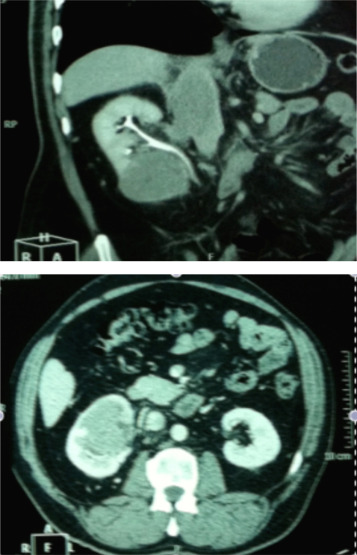

Paciente de 53 anos de idade, sexo masculino, não fumador, foi encaminhado para a consulta de urologia por uma lesão incidental do rim direito, diagnosticado em ecografia renal de rotina. Assintomático e sem antecedentes relevantes. A tomografia computorizada abdominal (fig. 1) mostrou uma lesão sólida com 67 x 65 mm na metade inferior do rim direito com invasão do seio, veia renal, veia cava inferior (VCI) e aurícula direita, e cuja angiorressonância magnética confirmou o diagnóstico. O ecocardiograma transtorácico mostrava uma massa ecodensa, heterogénea, imóvel na aurícula direita, emergindo da VCI compatível com o trombo.

TC abdominal mostrando lesão sólida com 67x65mm, na metade inferior do rim ...

Figura 1.

TC abdominal mostrando lesão sólida com 67 x 65 mm, na metade inferior do rim direito com invasão do seio, veia renal e veia cava inferior (VCI).